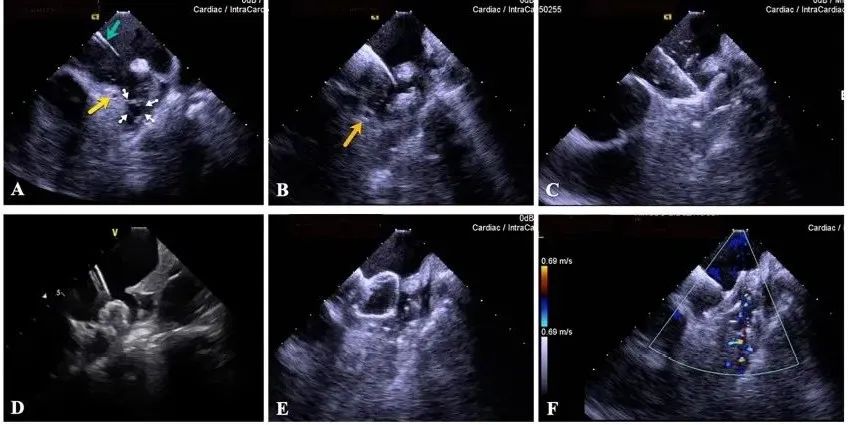

一種與心導管檢查相結合的超聲心動圖診斷新興技術,通過將超聲探頭置于心腔內部,發(fā)射并接收超聲信號,來精確獲取心臟解剖結構、心臟血流動力學等信息的實時成像。與其他影像技術相比,ICE技術具有操作簡單、無輻射、安全性高、手術效率高、實用等優(yōu)勢,ICE在很大程度上有望取代經食道超聲心動圖(TEE),成為電生理和結構性心臟病領域的理想成像方式。

目前ICE技術已被應用于左心耳封堵、房顫射頻消融、二尖瓣成形、房間隔缺損封堵等多種心臟介入手術,應用場景主要圍繞心臟電生理、結構性心臟病等領域,目前以電生理應用為主。數(shù)據顯示,我國結構性心臟病介入器械市場規(guī)模已從2017年的4億元增長至2021年的20億元,年復合增長率達48.3%;預計到2025年,該市場規(guī)模將達到104億元,可以預見ICE市場規(guī)模也將同步高速增長,未來市場發(fā)展空間廣闊。

心腔內超聲(ICE)技術壁壘極高,國內主要廠商核心部件仍舊為進口,集成了超聲和圖像處理最前端技術,包括超聲探頭、線纜、軟件成像算法等,是當前內窺超聲方向最具挑戰(zhàn)的領域。ICE的應用經歷了2D平面成像、3D三維立體成像、以及4D的實時三維立體成像階段。